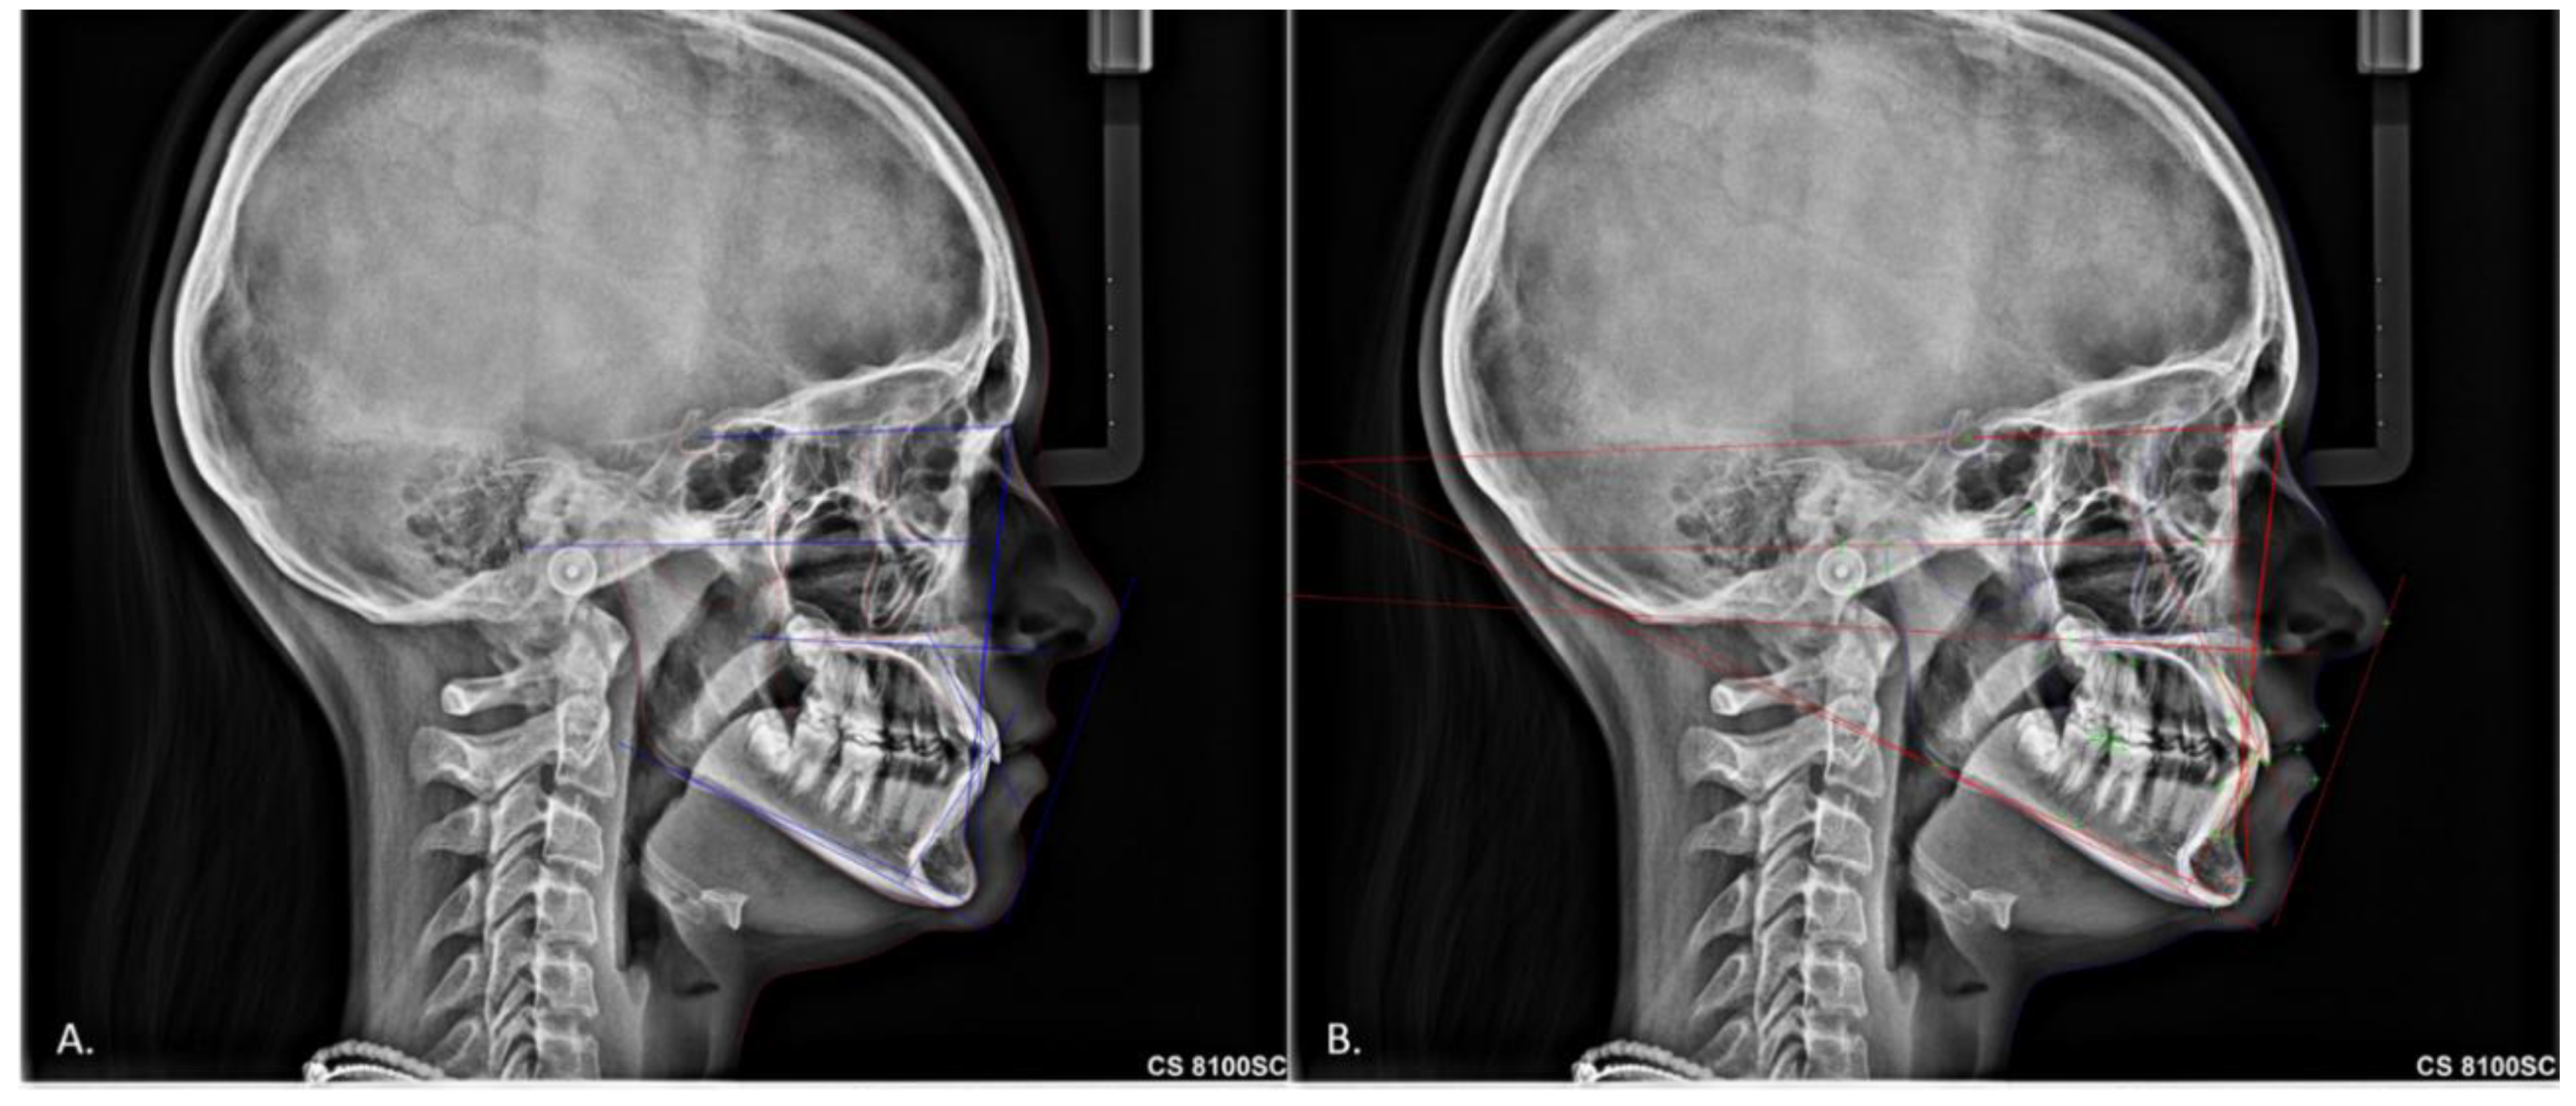

2. Materials and Methods